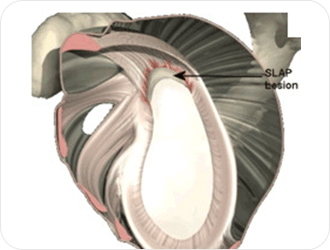

팔을 어깨 위로 반복적으로 들어올리는 경우나 어깨관절에 직접 가해지는 물리력에 의해 발생하는 경우, 40대 이후에서 회전근개 건병증과 연관되어 발생하는 경우 등 여러가지 상황이 있을 수 있습니다.

고령층에서 상부관절와순 후방부의 경도 분리는 정상적인 범주로 간주됩니다. 야구에서 던지는 동작이라든지, 머리를 감는 동작, 수영에서 팔을 뒤로 드는 동작 등을 할때 통증이 발생합니다. 젊은 환자의 경우는 수술적 치료가 필요합니다.

상부관절와순 파열은 형태에 따라 치료방법에 약간씩 차이가 있으나 대개 헤어진 부위는 관절내시경으로 매끈하게 다듬고 관절와에서 떨어져 나와 불안정한 부위는 관절와에 붙이는 수술을 하게 됩니다.